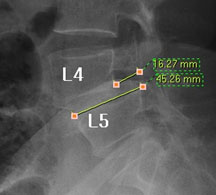

모커리한방병원 조○○ (79, 여) 척추전방전위증 2단계 실제치료사례 이미지

조○○ (79, 여) 척추전방전위증 2단계 입원치료기간 : 28일

입원시 퇴원시

허리 통증지수(NRS) 8 0

엉덩이 통증지수(NRS) 7 0

통증없이 걷는거리(m) 20m(보조기 착용) 150m(보행기 없이)